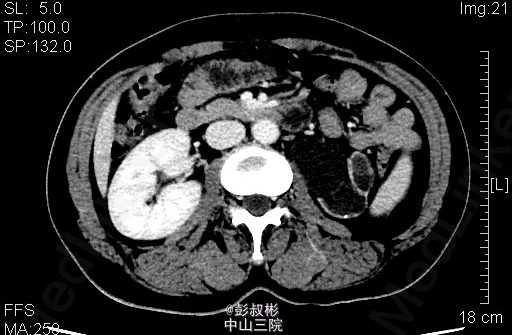

患者女性,47岁,左腹部胀痛1月余。既往有“双肾结石”病史10余年。其余见双肾CTU。根据检查判断肾的病变?